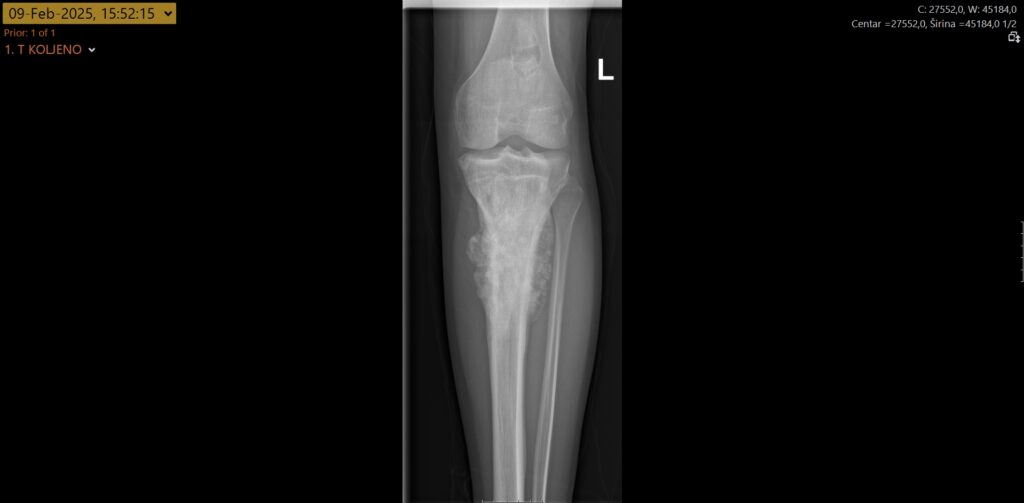

Na Zavodu za ortopediju i traumatologiju Kliničkog bolničkog centra Split po prvi put je obavljen zahvat odstranjenja izrazito malignog tumora osteosarkoma tibije. Riječ je o jednom od najmalignijih tumora ljudskog tijela uopće, a kako se ovakvi zahvati gotovo i ne obavljaju u zdravstvenim ustanovama u RH, pacijente se za obavljanje zahvata upućivalo u inozemstvo.

No to više nije potrebno jer je zahvat uspješno obavljen u splitskoj bolnici, i to baš mladom Splićaninu, koji se dobro oporavlja. Tijekom zahvata u potpunosti mu je odstranjen koljenski zglob te gornjih 17 cm goljenične kosti koji su zamijenjeni posebnom tumorskom protezom i nadomjestkom – implantatom za odstranjenu kost. Potom je nastali defekt primarno zatvoren i pokriven kožno-mišićnim režnjem.